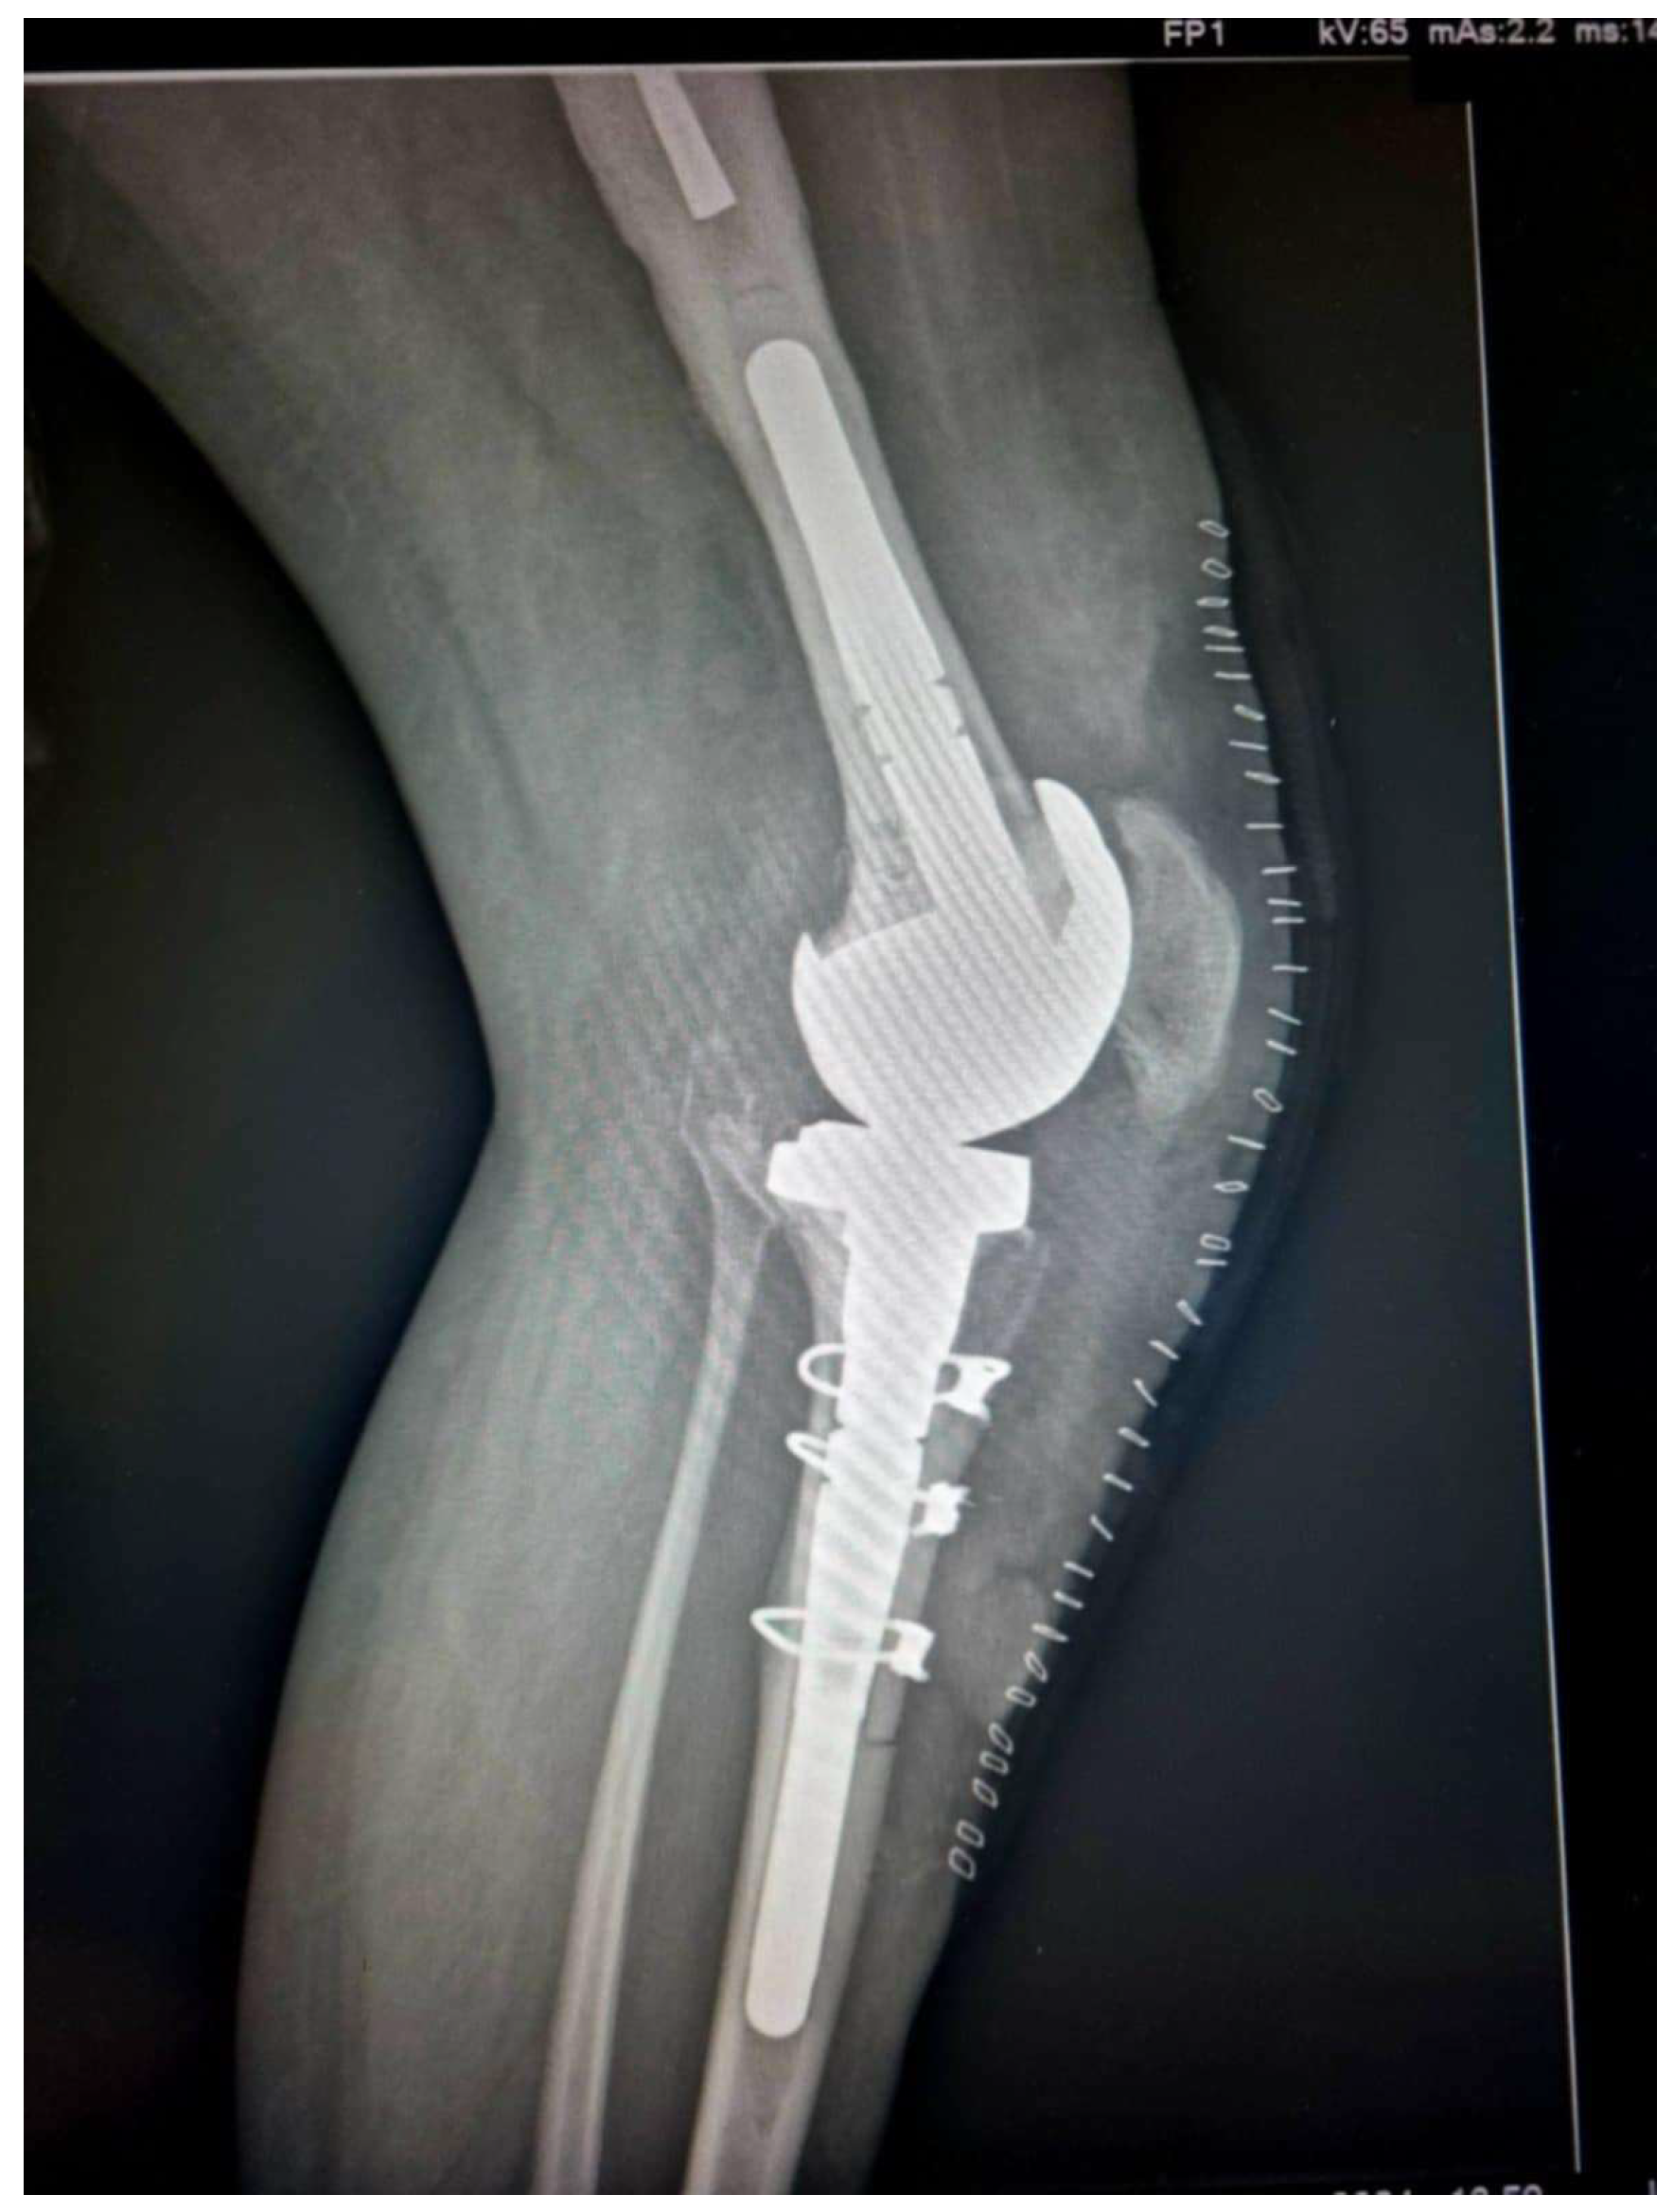

Figure 4. Postoperative radiograph demonstrating the proper reduction of the bone flap (Case 3).

Caution must be given when passing behind the posterior tibia so as not to traumatize the neurovascular bundle. The passer must cross as close as possible to the posterior cortex of the tibia. Afterwards, the tibial component was removed and re-implanted, with bone cement applied solely to the central-metaphyseal region (Figure 3 and Figure 4). Any cement excess was removed from the osteotomy site.